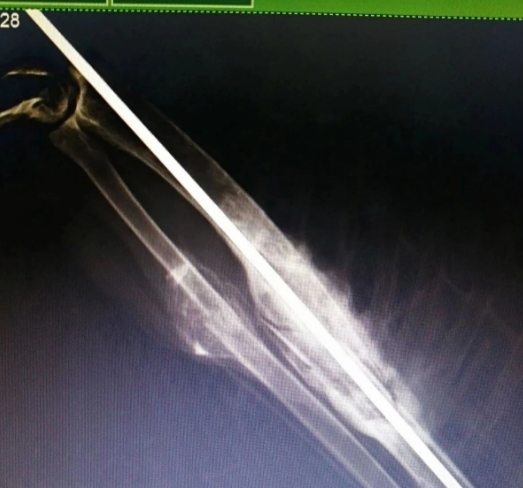

通过多天的筹款,很多野生动物保护志愿者解囊相助,共计5232.46元的爱心善款向巴尔虎草原汇集。 在北京的张拥军医生看了X光片后表示可以进行手术。

北京的张拥军医生看了X光片后表示可以进行手术

双龙带着雕鸮到新右旗人民医院拍了放飞前的最后一张X光片

2019年3月15日上午,双龙带着雕鸮到新右旗人民医院拍了放飞前的最后一张X光片,无需挂号,一路绿色通道。医生告诉双龙骨头断裂处已长出骨甲,恢复得特别好。

“你看,你看,这是你的翅膀,你痊愈啦,就该回家了!”在医院的电脑前,双龙依旧用哝哝软软的蒙语与雕鸮交流……